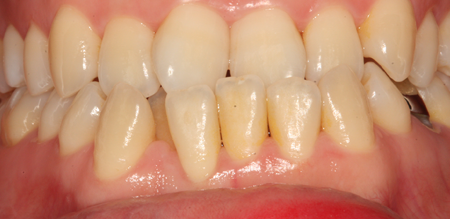

치주치료 전후사진

B

A